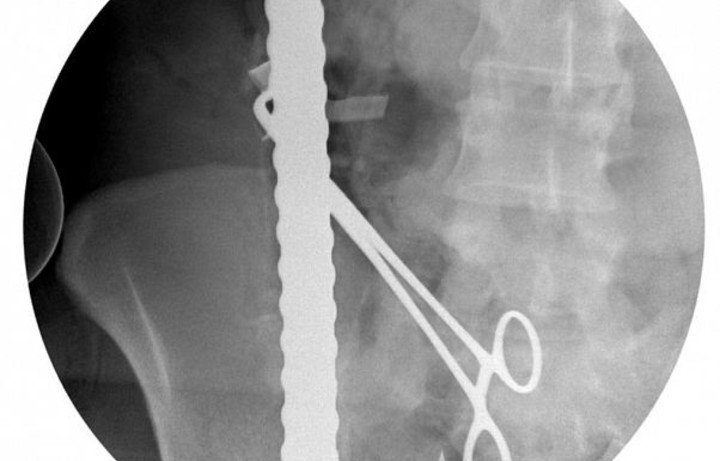

سعودی ڈاکٹروں نے غیرملکی کے جسم سے سلاخیں نکال کر زندگی بچا لی